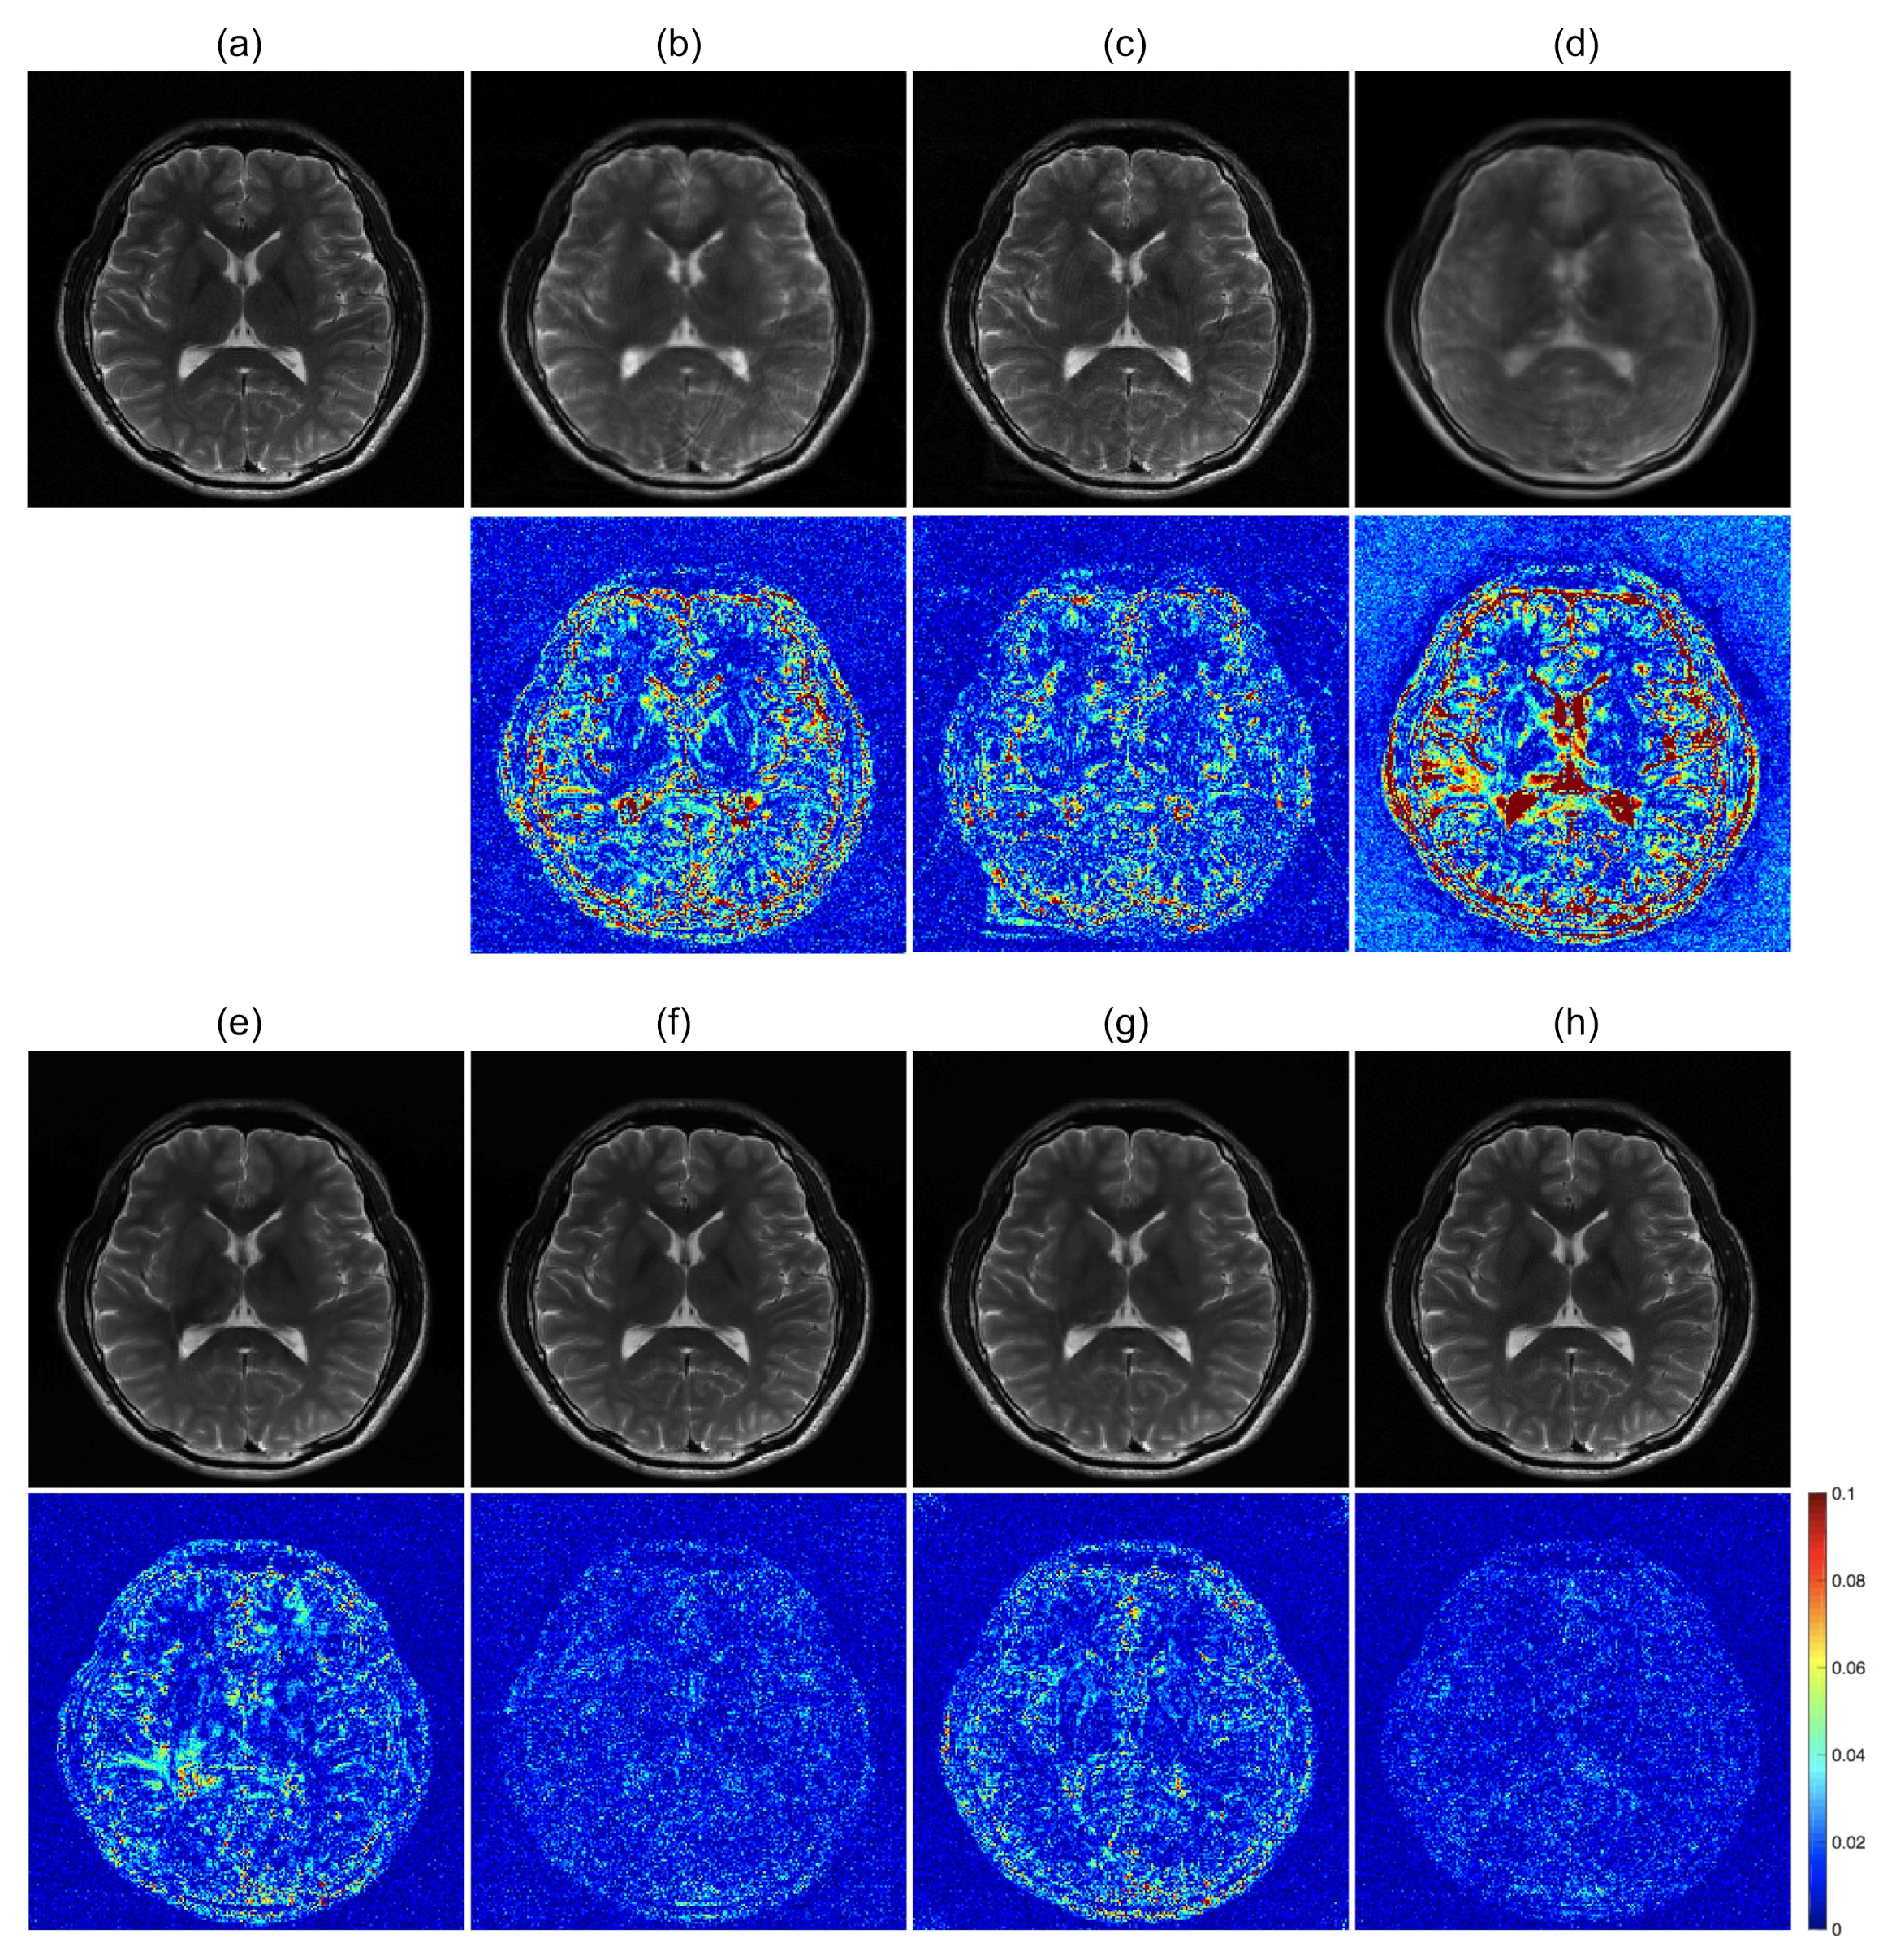

To further optimize the proposed network for image reconstruction, two different losses were additionally calculated along with the baseline loss function of the Euclidean distance: adversarial loss and perceptual loss. The effects of the loss functions were analyzed for the undersampled k-space data with R = 4. The ETER-net with different loss functions was also compared with two different image-domain to image-domain reconstruction methods, DFU [27] and DAGAN [19], and a k-domain to k-domain reconstruction method, k-space deep learning for accelerated MRI [16]. Figure 7 shows the result images and errors, and Figure 8 shows the quantitative analysis of the reconstructed images. Figure 7b,c show a substantial amount of image artifacts and aliasing patterns, owing to the regular subsampling of the input k-space data. In contrast, the proposed methods show quality results, and the aliasing artifacts are eliminated in these images (columns (e–h)). By comparing the images reconstructed with various loss functions, it can be concluded that the loss functions, including the Euclidean distance, adversarial loss, and perceptual loss, provided the best performance in terms of image quality.

Figure 7.

Comparison of previous methods with the proposed method. first and third row: Magnitude images. second and fourth row: Corresponding error maps in the 1/10 range. (a): Ground truth magnitude images (label images). The images are reconstructed by (b): DFU, (c): DAGAN, (d): k-space deep learning, (e): baseline loss, (f): baseline loss + perceptual loss, (g): baseline loss + adversarial loss, and (h): baseline loss + adversarial loss + perceptual loss.